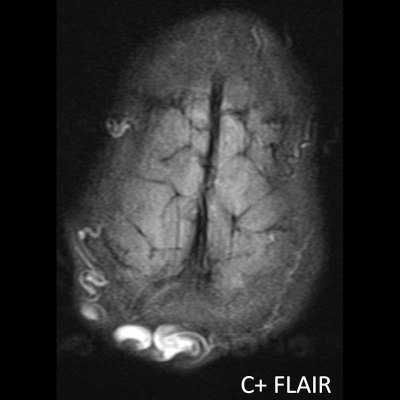

1. A) Kontrastlı FLAIR aksiyel görüntüde ve sagital T2A görüntüde vertekste orta hatta cilt altında dilate tortiyoze vasküler kollateraller (oklar). Paryetal kemikte orta hatta defekt (ok) ve defekt ile ilişkili vasküler yapıların cilt altı yumuşak dokulara uzanımı izlenmektedir.